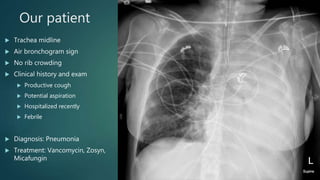

Our patient

 Trachea midline

 Air bronchogram sign

 No rib crowding

 Clinical history and exam

 Productive cough

 Potential aspiration

 Hospitalized recently

 Febrile

 Diagnosis: Pneumonia

 Treatment: Vancomycin, Zosyn,

Micafungin

Our patient  Tracheamidline  Air bronchogram sign  No rib crowding  Clinical history and exam  Productive cough  Potential aspiration  Hospitalized recently  Febrile  Diagnosis: Pneumonia  Treatment: Vancomycin, Zosyn, Micafungin